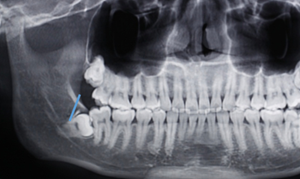

右下智齒去骨范圍如何?分冠線如何?怎樣才能最快時間能把這顆牙拔出來?

阻生牙的阻力分析及去除阻力的方法問題一:這顆智齒去骨范圍如何?分冠線如何?

答:本x線片示48近中低位埋伏阻生,且牙根緊鄰下牙槽神經(jīng)管,拔除時需注意充分去除近中方向的牙體冠方阻力及遠(yuǎn)中的牙槽骨阻力,挺出牙根時盡量做到一次完成,減少牙根與神經(jīng)管的摩擦,降低神經(jīng)受損風(fēng)險。

遠(yuǎn)中:骨阻力 近中:牙體冠方組織

第一:確定阻力去骨的范圍: